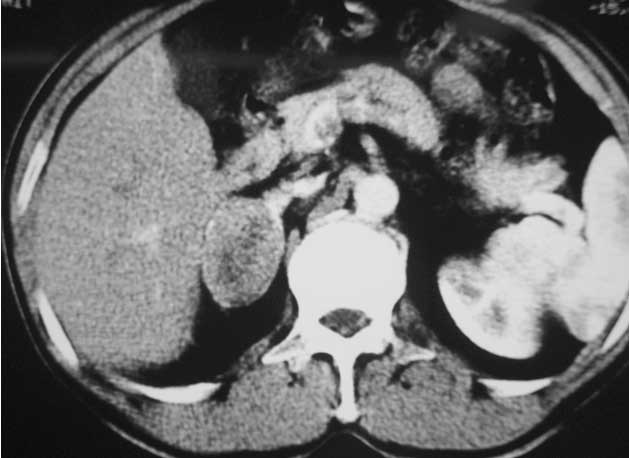

Bệnh nhân Nguyễn Tr. Th.50 tuổi, vào viện vì đau tức hông phải. Tiền sử có cắt u đại tràng phải cách 5 năm và cắt gan trái được 2 năm. Bệnh nhân hoàn toàn khỏe mạnh, CT bụng cho một u ở thượng thận bên phải đường kính đo được 8cm và các xét nghiệm cận lâm sàng khác kể cả cortisol máu, chưa phát hiện thêm thương tổn gì. Bệnh nhân được mổ bóc u thượng thận qua lối sau và chẩn đoán giải phẫu bệnh là ung thư vỏ thượng thận.

Hình 2: Hình ảnh CT bụng